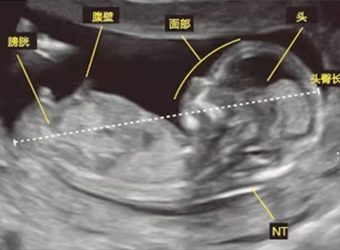

NT检查是一项孕检,主要是为了筛查唐氏综合征的儿童,也是一种超声检查,据说NT图男女宝宝是可以看出区别的,那么NT男女宝宝区分图片是什么,三个月的NT可以看…

在国外还是有通过超声胎儿性别的方法的,其中最简单的方式就是看宝宝的第二性征,那么NT检查图看男女看哪个角度呢,NT胎儿男女区别对照图,更多关于生男生女的…

NT检查属于孕检的一种,医学名称叫颈后透明带扫描,这种检查一般是在孕期的11到13周做,那么NT检查单子上有男女标志吗,更多关于生男生女的相关内容尽在妈妈育…